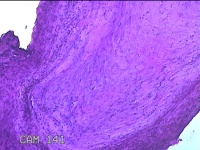

右侧肘后包块

性别

男

年龄

59岁

临床诊断

脂肪瘤

一般病史

发现右侧肘后包块1年余,无明显疼痛及不适。

标本名称

大体所见

灰白暗红色肿物1.3x0.5x0.3cm一个,表面糜烂。